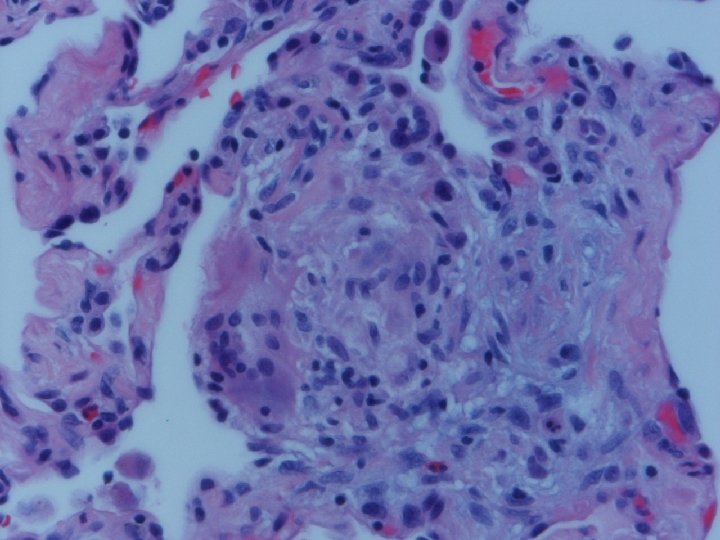

Lung biopsy revealed chronic bronchiolitis/ hypersensitivity pneumonitis (extrinsic allergic alveolitis) with opinion from Mayo Clinic path arriving on 3/30/04. “Hot tub lung due to MAC”. I recommended Prednisone 20 mg. daily, but she had major psychiatric complications for which Seroquel was added and prednisone reduced. X-ray, spirometry, and symptoms resolved. Prednisone tapered and stopped in late May. Recurrence of symptoms and rash in August/September.

Acute HP • Clinical-Abrupt • Lab-ESR, IGG, RA, CRP, LDH, BAL lymphocytosis, restrictive physiology • CXR-micronodular interstitial, but freq. normal-HRCT needed, but not absolute • Histopathology-poorly formed, noncaseating interstitial granulomas, monos, giant cells

Subacute or Intermittent HP • Clinical-gradual cough, dyspnea, fatigue, anorexia, wt. loss, malaise; tachypnea and rales • Lab-BAL lymphocytosis, hypoxemia. Restrictive or mixed spiro, decreased DLCO • CXR-nml, micronodular, reticular. HRCT micronodules, ground glass, emphysema, fibrosis • Histopathology- noncaseating granulomas, bronchiolitis with or w/o organizing pneumonia

Chronic Progressive HP • Clinical-insidious cough, dyspnea, fatigue, weight loss, clubbing • Lab-not very helpful-BAL lymphocytosis but not crisp; restrictive, but usually mixed. DL always reduced, and exertional hypoxemia • CXR-may be normal, but usually progressive fibrosis; emphysema often • Histopathology-granulomatous pneumonia, BO with or w/o OP, fibrosis